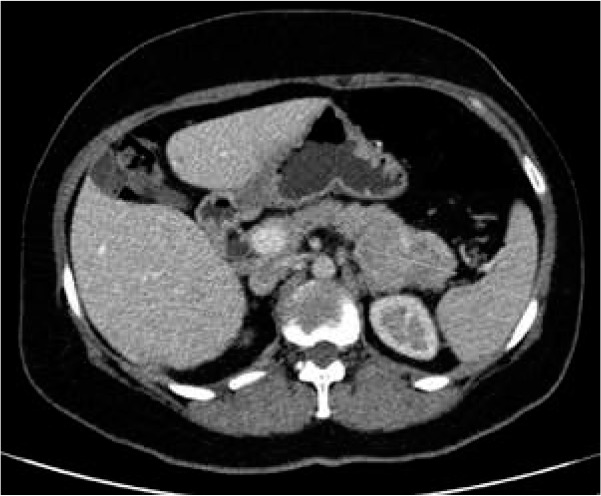

Taking into account an unusual clinical picture and undiagnostic histopathological results, the paraneoplastic syndrome was suspected. The second abdominal ultrasonography disclosed round lesions in the liver – 24 mm in the right lobe and 21 mm in the left lobe. A contrast-enhanced computed tomography of the abdomen confirmed multiple hepatic tumours and low enhancing pancreatic tail mass 56 × 37 mm (Figure 4). The serum glucagon level was highly elevated 2275 ng/l (norm < 209) as well as the levels of chromogranin A 17.2 ng/ml (0–6) and LDH 224 U/l (100–214). She was referred to the Oncology Department where she underwent a needle biopsy of a hepatic lesion that confirmed the neuroendocrine tumour diagnosis (NET G2, Ki-67 3%) with the primary tumour in the pancreas. Afterwards the patient was referred to the Endocrinology Department where she started lanreotide injections of 120 mg once a month. The surgical removal of the tumour was not performed due to the patient’s refusal. For the last 12 months the disease has remained stable.

Figure 4

Computed tomography (CT) of the abdomen showing low enhancing pancreatic tail mass measuring 56 × 37 mm